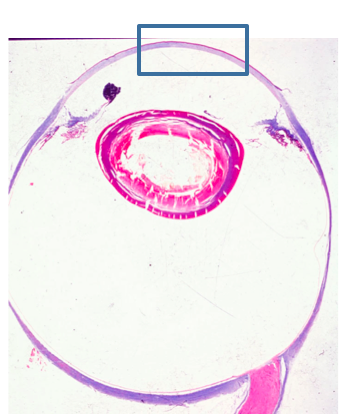

What is outlined in the rectangle?

Cornea